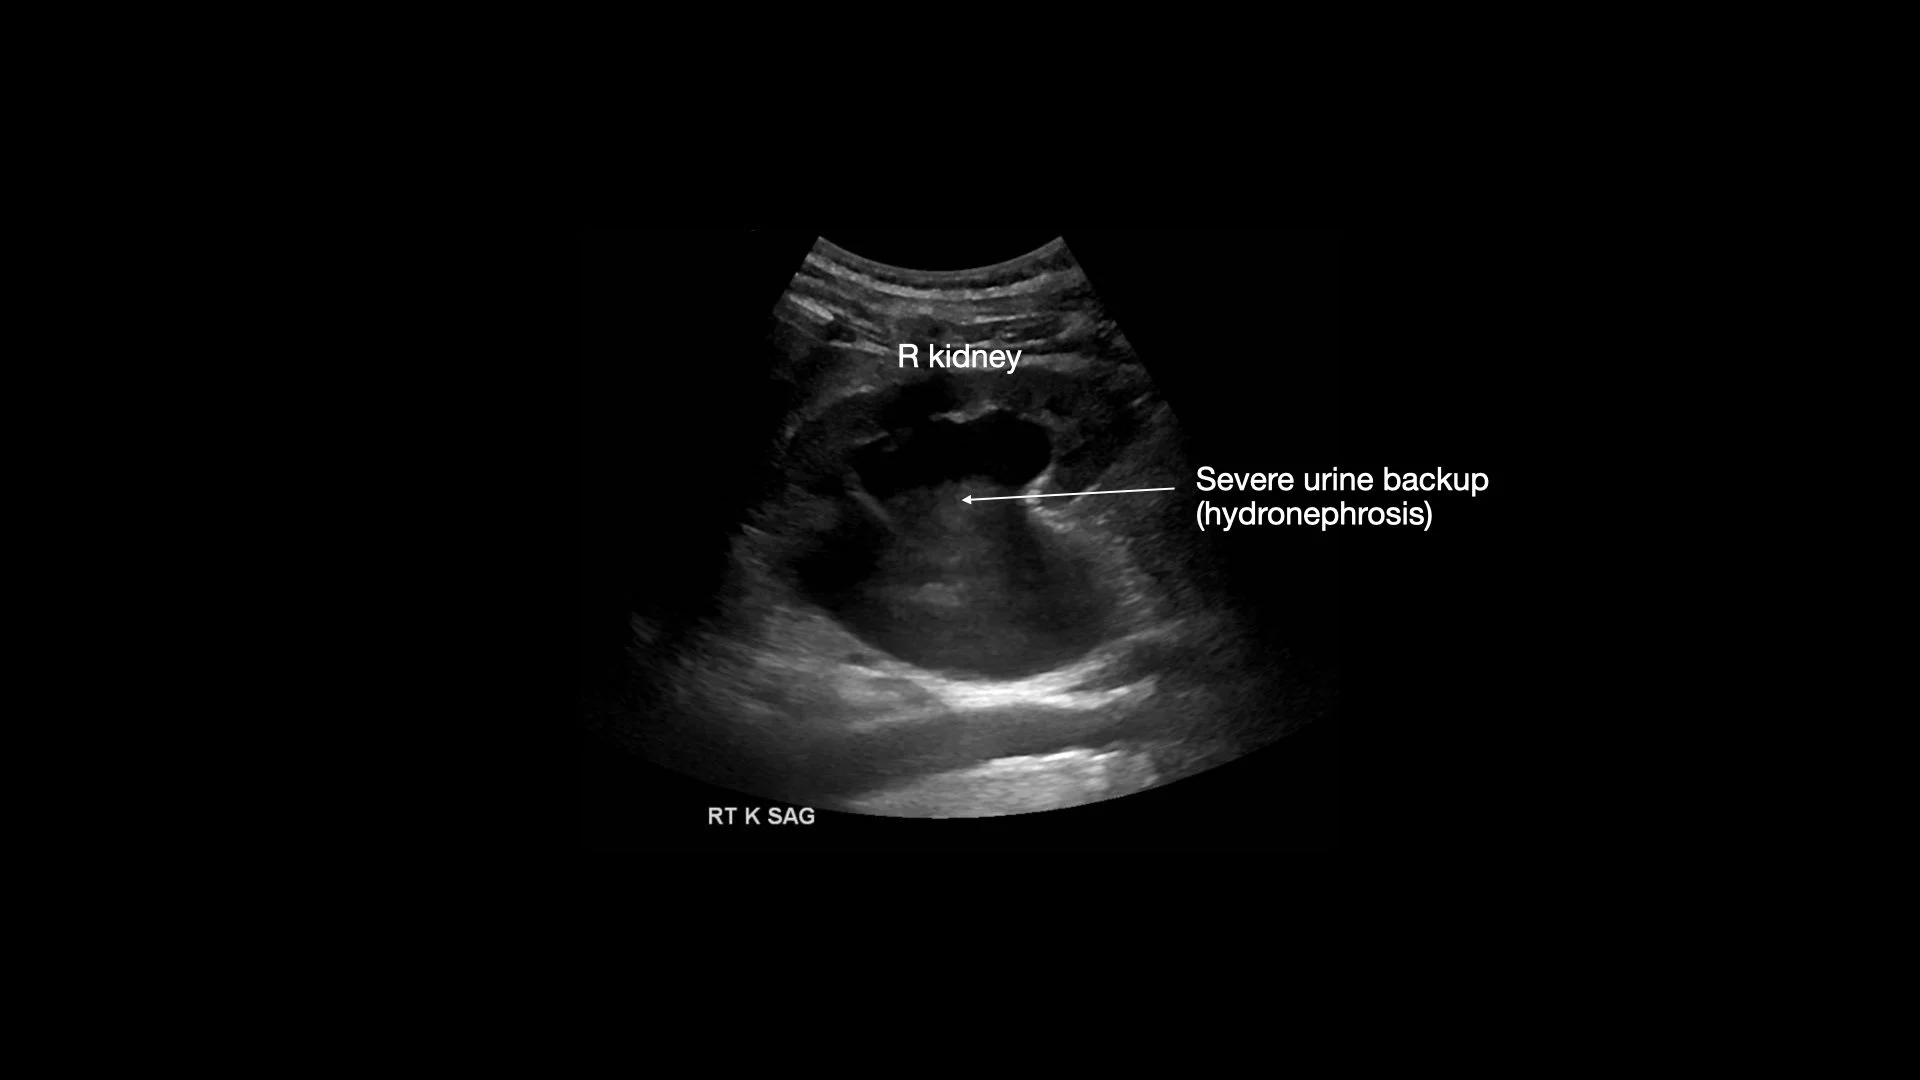

Ultrasound of his right kidney in the hospital showing chronic obstruction with severe hydronephrosis

He went years between the first episode and second thinking the problem was fixed. He went a few months after the first recent hospitalization thinking he was ok again. He noted after his foley was removed a week after his first hospitalization that he did not urinate for 36 hours. He then started urinating again. Couple months later, he was back in the hospital again with obstruction and complications of kidney injury. Foley was again placed with some improvement in his kidney function but he has likely developed long term kidney damage due to these episodes.

Point of care ultrasound (POCUS) of the bladder and kidneys takes minutes to perform and would have revealed if he was retaining urine despite medical treatment years ago, and between his first and second hospitalization if his trial without foley had failed within those first 2 days when he wasn’t urinating. This highlights how POCUS could have potentially prevented long term kidney damage if complications are caught early.